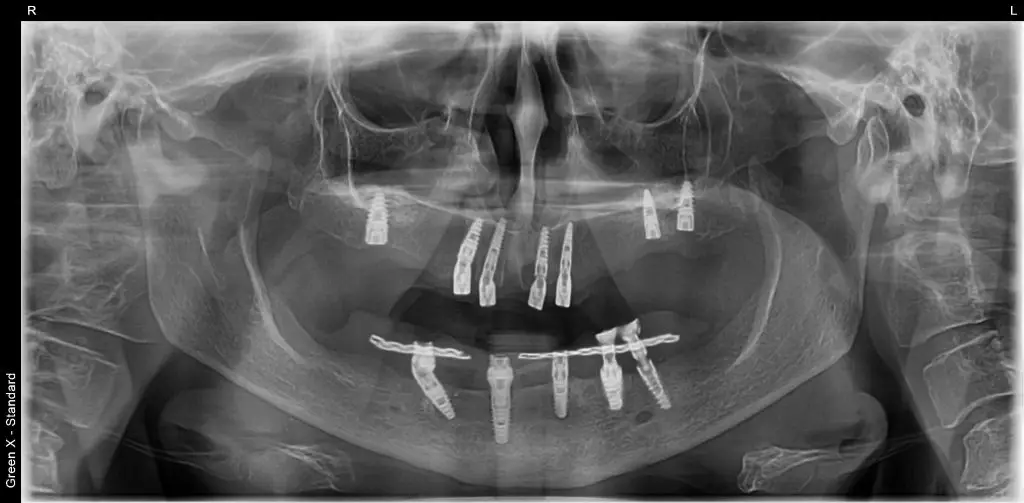

Am extras dintii irecuperabili, am practicat lifting de sinus maxilar (in unele situatii nu poate fi evitat) si am inserat 6 implanturi.

Pe implanturile frontale, a 2a zi, s-a inserat in cavitatea orala lucrarea provizorie pe implanturi.

Dupa 6 luni, s-au realizat lucrarile finale pe implanturi, la maxilar si la mandibula.